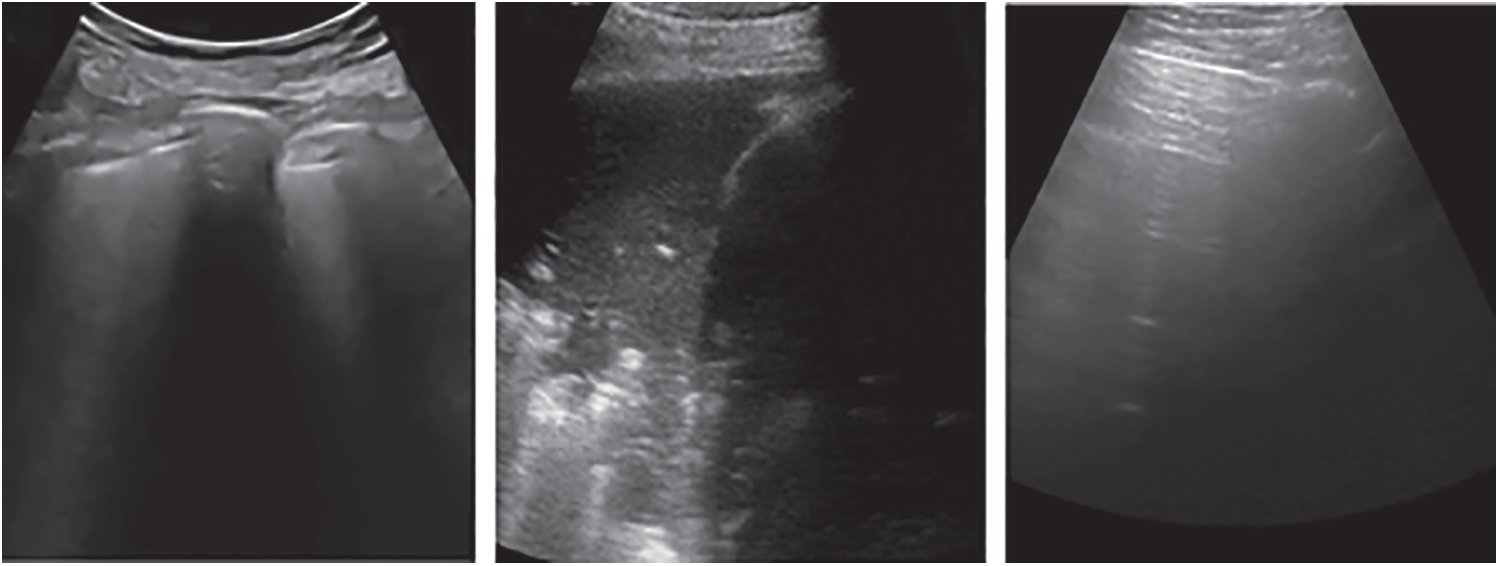

The public lung US POCUS database [9] has been used in this study. The available images of this dataset include 911 images extracted from 47 videos using a convex US probe (Last Access: 20 September 2020). They divided into three different classes of US images as shown in Fig. 2. Total number of images for infectious COVID-19, bacterial pneumonia and the healthy lung are 339 images, 277 images and 255 images, respectively. Small subpleural consolidation and pleural irregularities can be shown for the positive case of COVID-19, while dynamic air bronchograms surrounded by alveolar consolidation are the main symptoms of bacterial pneumonia disease.

Figure 2: Three different cases of US images present the positive COVID-19 (left), bacterial pneumonia (middle), and healthy lung conditions (right)